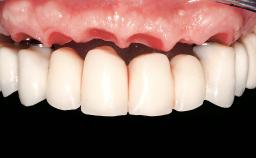

Immediate Loading of Eight Implants in the Maxilla and Six Implants in the Mandible and Final Restoration with Three-Unit and Four-Unit FDPs

Extensive scientific evidence has confirmed that immediately loaded implants with fixed full-arch provisional restorations can osseointegrate with success rates similar to conventionally or delayed loaded implants. A number of immediate-provisionalization techniques for edentulous jaws have been described. Some protocols differ when it comes to prefabricated provisional templates versus complete denture conversion; intrasurgical impressions versus direct relining; and cemented versus screw-retained provisional restorations. In this context, complete-denture conversion has been proposed for either intrasurgical impressions or direct relining. Another possibility is the utilization of a prefabricated provisional to be adapted either in the mouth (by direct relining) or in the laboratory (on a working model obtained from an intrasurgical impression).

Defining Characteristics Fully edentulous upper jaw to be rehabilitated with an implant-borne fixed dental prosthesis